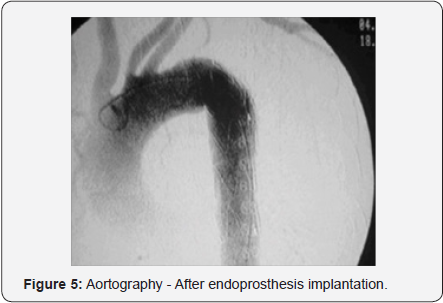

Endovascular thoracic aortic repair (TEVAR), refers to the minimally invasive approach, which involves placing a stent graft in thoracic aorta or ring, possessing ample indications. The technique involves inserting modular grafts through the dissection of iliac or femoral arteries to thoracic aorta excluding vessel damage [7] (Figures 4 & 5). In the case of femoral arteries, after dissection of the right femoral puncture of femoral artery left there for the introduction of catheter, where there is the diameter of the aorta and if intralaminar defects are excluded, when inserted into the stent. Is recommended in victims with favorable anatomy, and has a more comfortable postoperative period and brief [7].